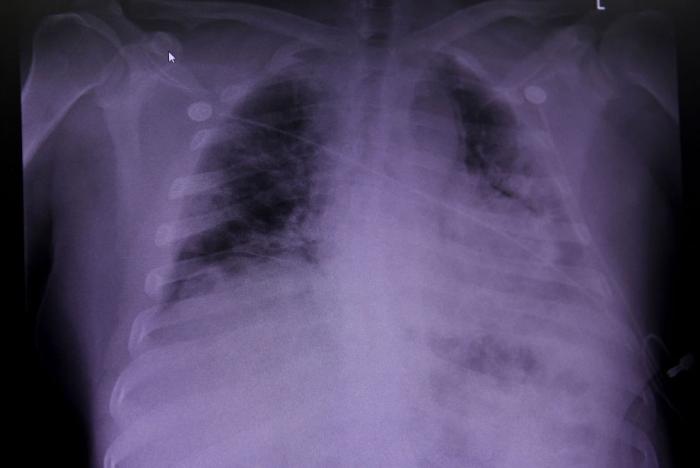

По последним данным ВОЗ, в мире выявлены уже более 17.6 миллиона случаев заражения, около 680 тысяч человек скончались. Тяжелее всего ситуация в США. Отправляемся на экскурсию в американский ковидный госпиталь в штате Техас.